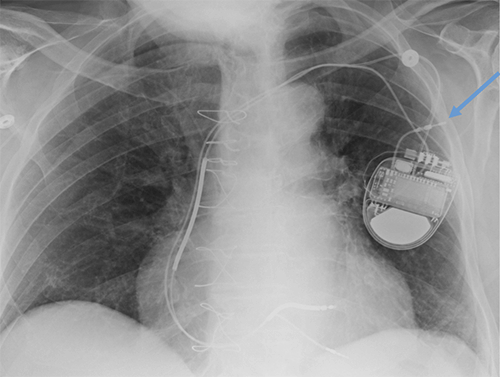

- CEID images with lead types:

Subcutaneous defibrillator